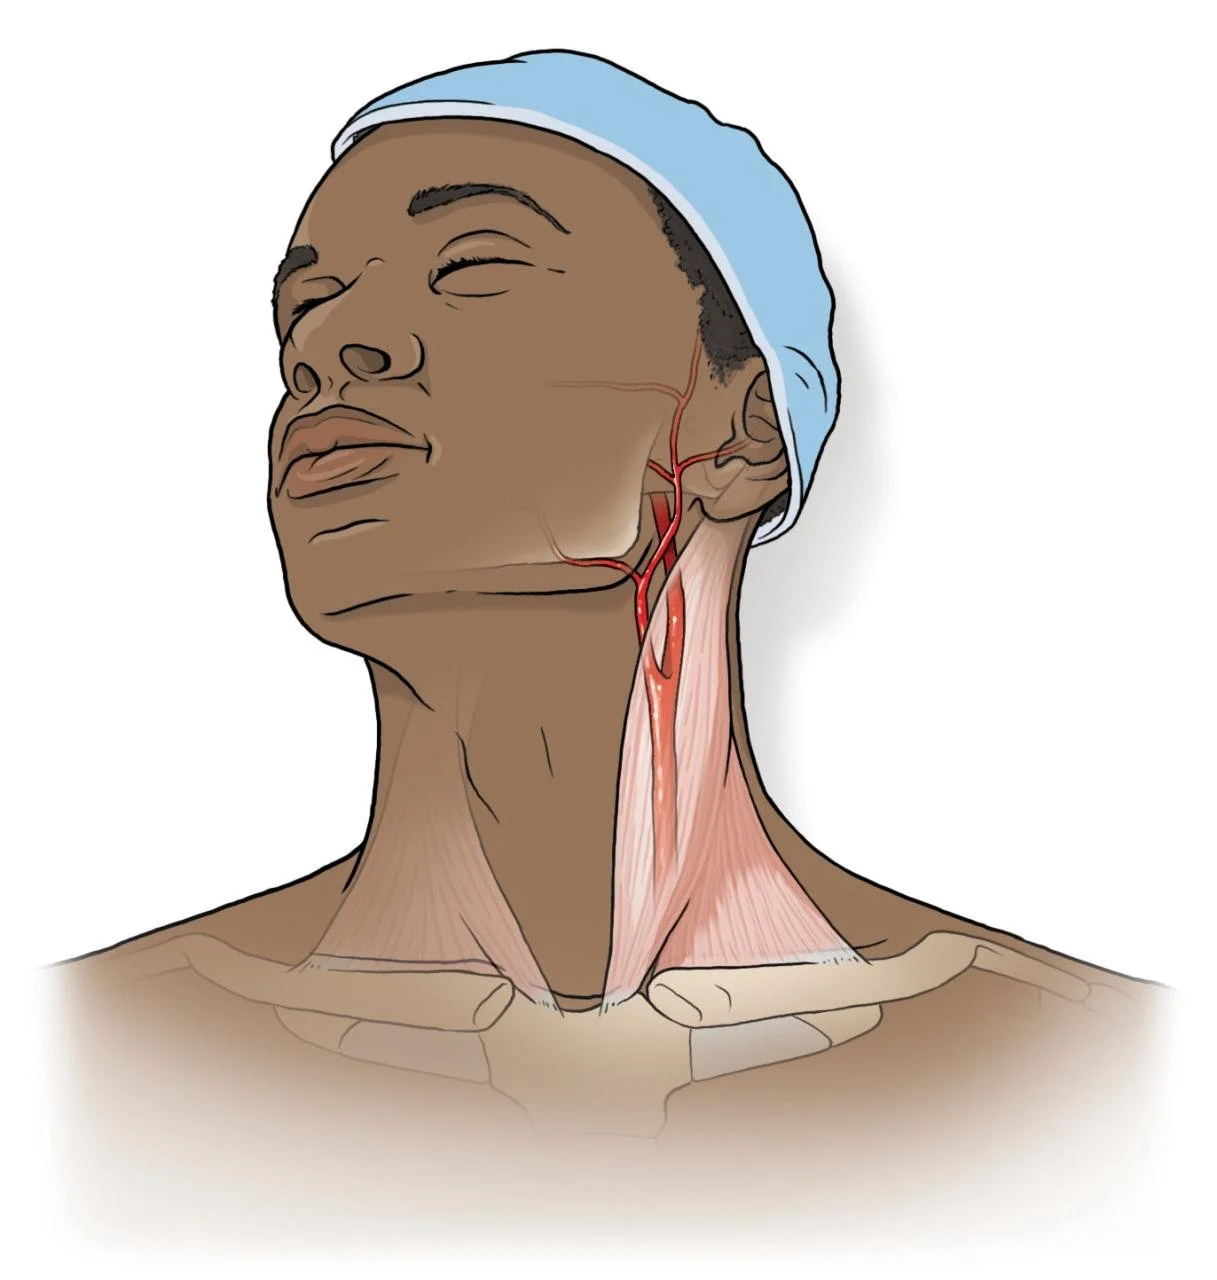

Medical Illustration

All images are works made for hire and are the exclusive property of the client. These are shown as sample purposes of my work only. For licensable work, please see my Illustration Services page.

Medical Illustrator for Precision Graphics, Lachina, and Human Kinetics Publishing (current)

Contract freelancer for many others, some examples of my work below.